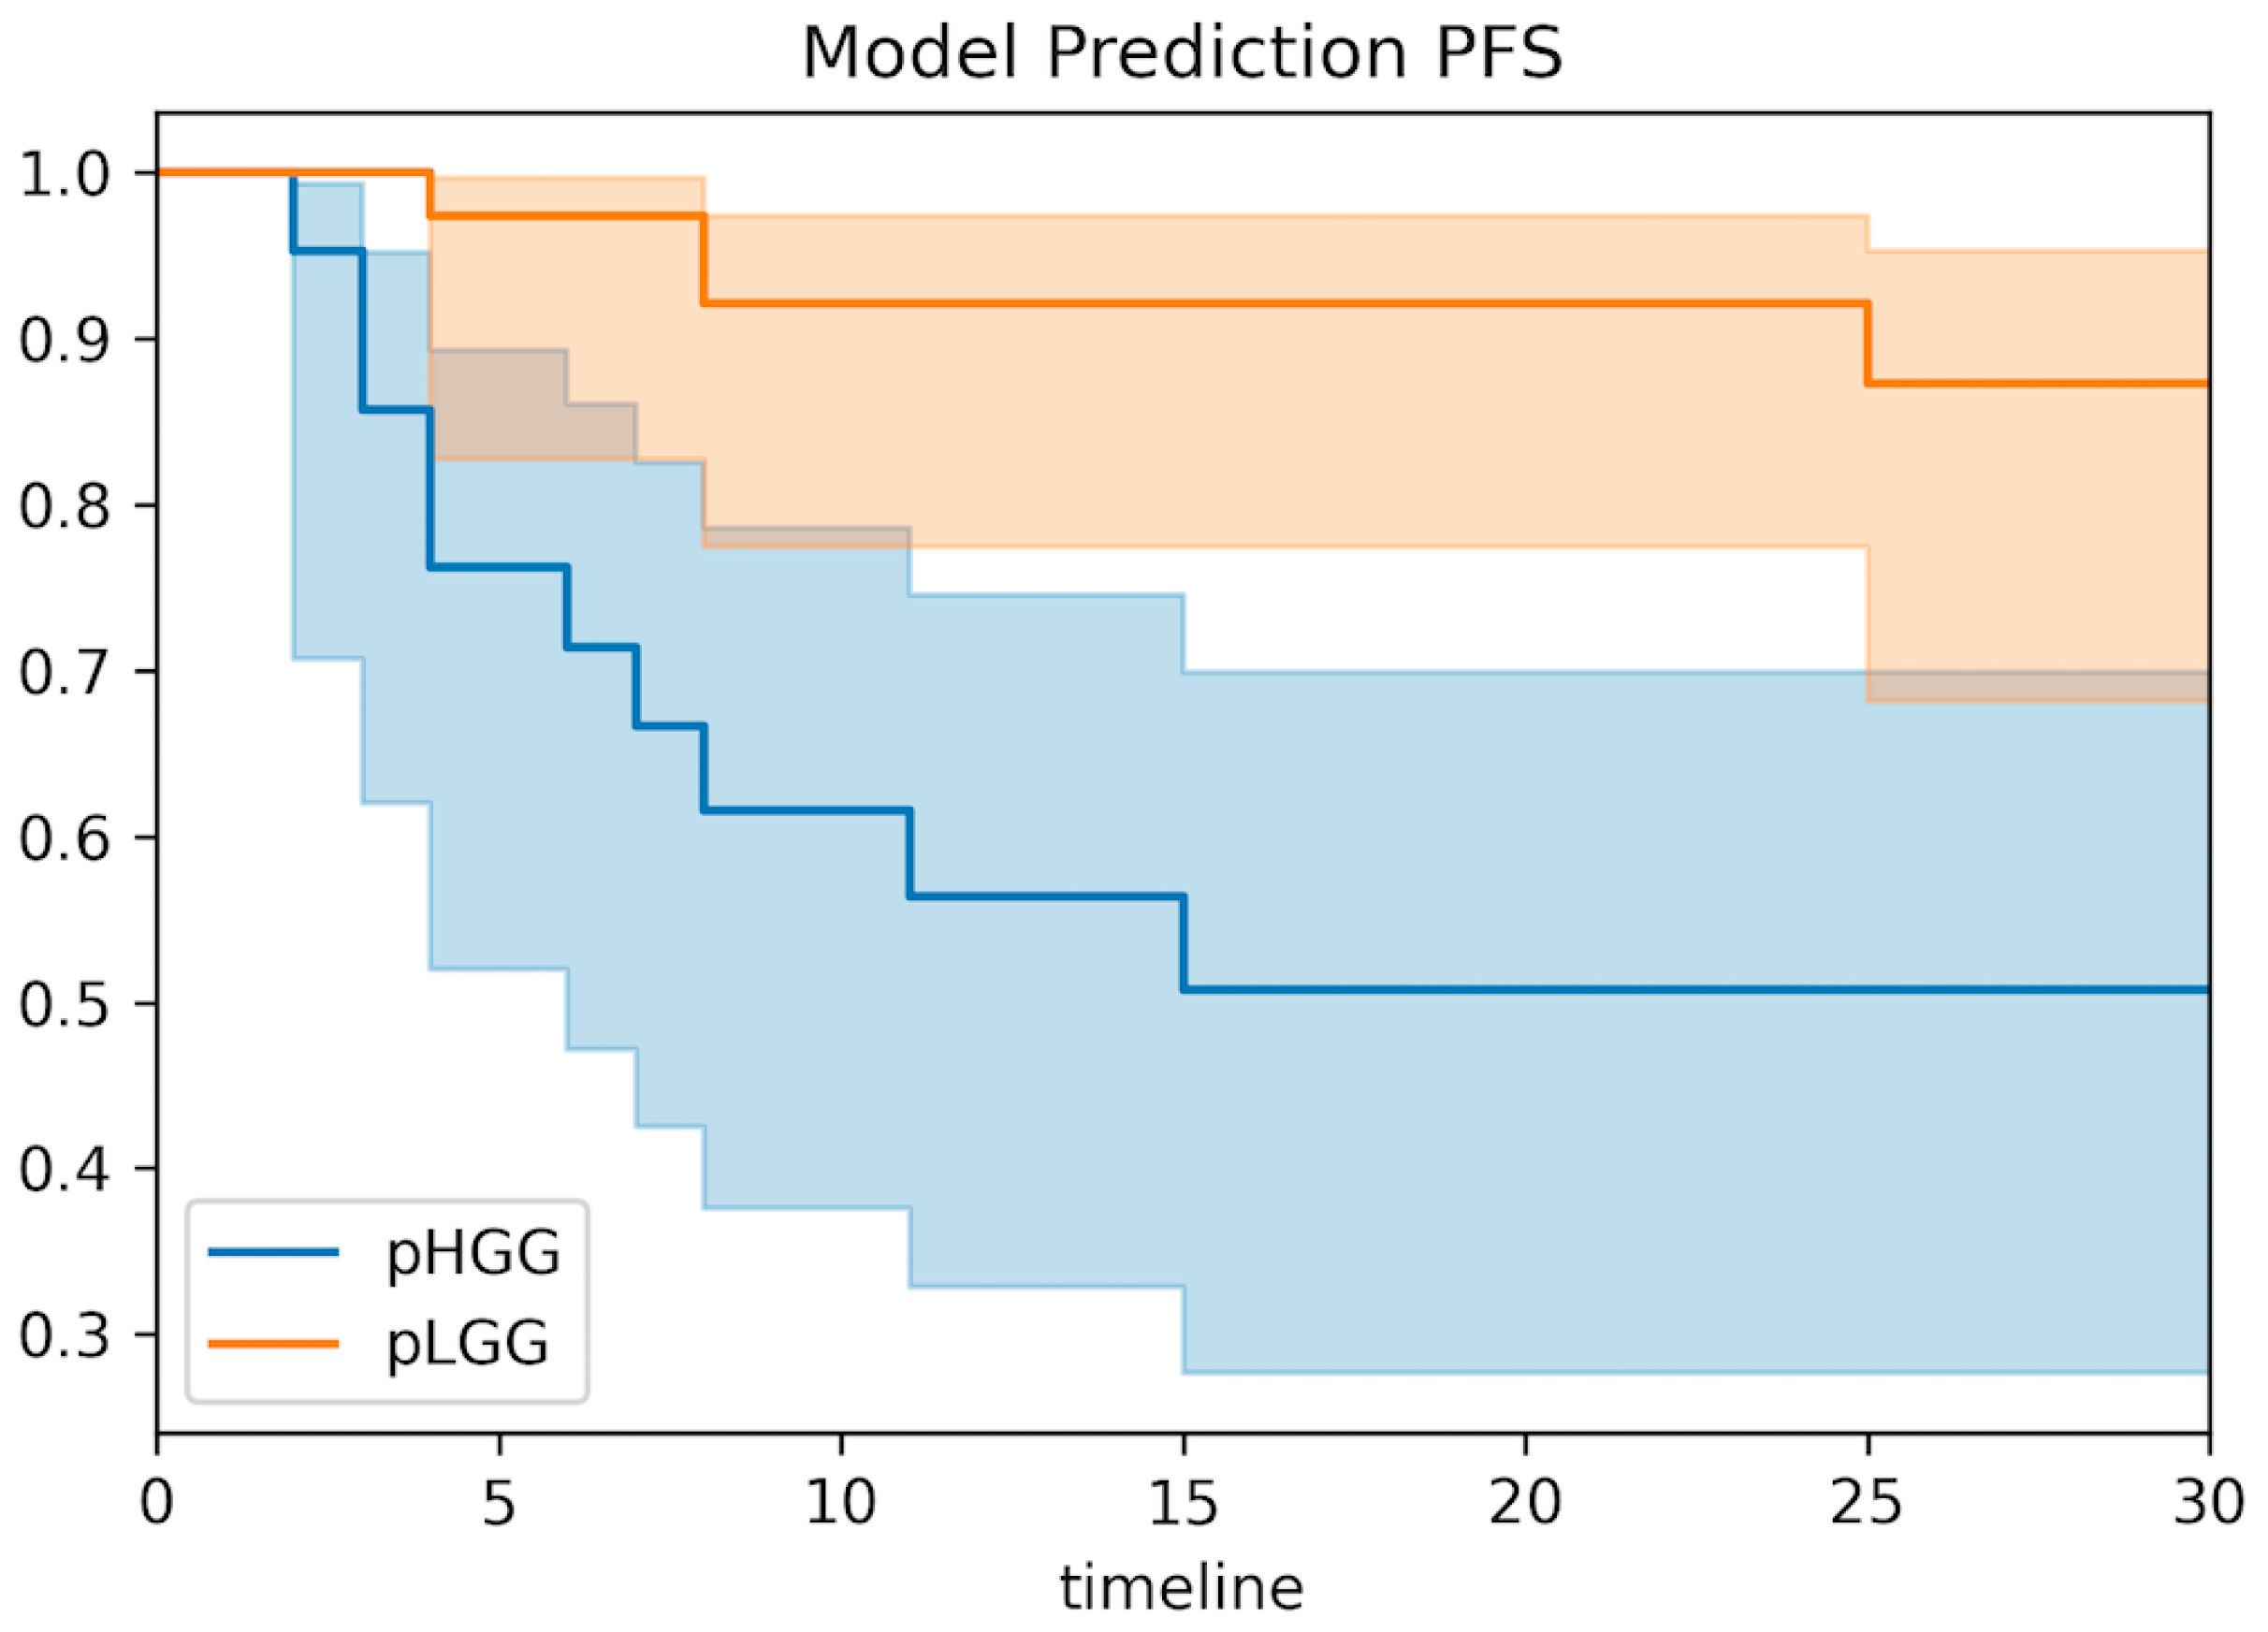

3.6. Clinical Correlations of the Predictive Model